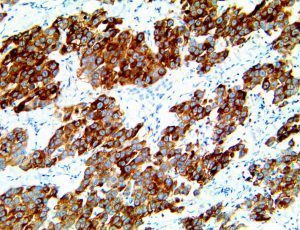

The first cytokines released are interleukin 1β (IL-1β) and tumor necrosis factor-α (TNF-α), which attract a variety of circulating white blood cells (WBCs) to the infection site, including neutrophils, monocytes, macrophages, and natural killer (NK) cells. This response, along with the antipathogenic chemicals released by these cells (i.e., complement), comprise the innate immune response. These cells directly attack the invading pathogen and also release additional cytokines, chief among them interleukin-1 and 6 (IL-6). IL-6 is essential for invoking the adaptive immune response, which calls T-cells, B-cells, and T helper (Th) cells to the infection site. IL-6 also stimulates further recruitment, proliferation and activation of macrophages.

It is the ICU physician who is most likely to witness one of the deadliest manifestations of the abnormal immunological response, the cytokine storm syndrome (CSS). This response is also referred to by some as the cytokine release syndrome (CRS). CSS is characterized by continuous activation and expansion of macrophage and lymphocyte populations, which secrete large amounts of cytokines, causing the cytokine storm. This massive cytokine release is akin to hemophagocytic lymphohistiocytosis (HLH) disease, a syndrome characterized by initial unchecked and persistent activation of cytotoxic T lymphocytes and NK cells.

Clinical and laboratory manifestations of HLH include fever, enlarged liver and/or spleen, neurologic dysfunction, coagulopathy, liver dysfunction, cytopenias (i.e., low levels of erythrocytes, leukocytes, and/or platelets), hypertriglyceridemia, hyperferritinemia, hemophagocytosis, and eventually diminished NK cell activity as the immune system becomes progressively paralyzed. HLH can be familial (primary HLH) or secondary to another disease process (sHLH), such as rheumatic disease, in which it is referred to as macrophage activation syndrome (MAS, characterized by elevated ferritin).